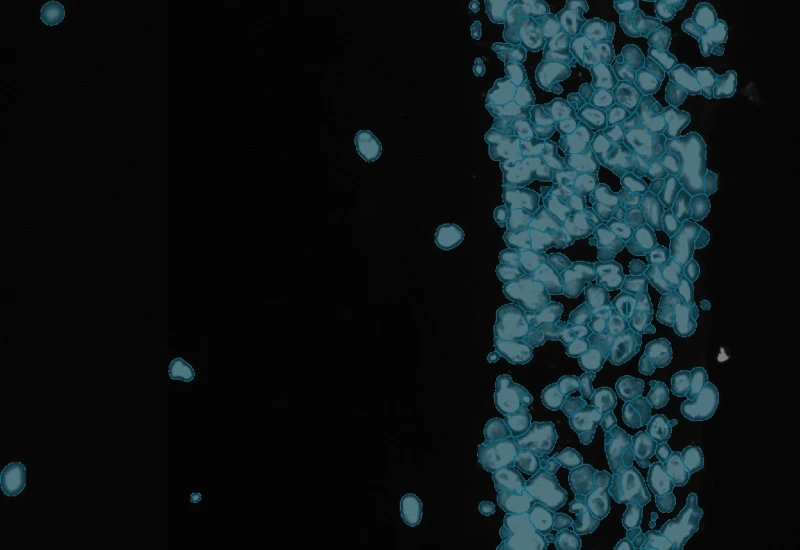

Stratify skin equivalents into dermis and epidermis, segment the stratum corneum, high/low suprabasal and basal layers, and quantify staining intensity, area, nuclei, and number/% of marker-positive cells for each layer.

The IF Artificial Skin App stratifies skin equivalents into differnet layers including dermis and epidermis and identifies nuclei based on appropriate staining. Further is subclassifies epidermis into stratum corneum, high suprabasal, low suprabasal, basal. The App outputs, area (µm2) of epidemis and dermis, area and mean staining intensity for each sublayer of the epidermis, total number of nuclei for each layer/sublayer and number/% of marker positive cells for each layser and sublayer.

Image courtesy of Prof. Florian Gruber

Detection of nuclei

Detection of dermis and epidermis

Detection of epidermis sublayers